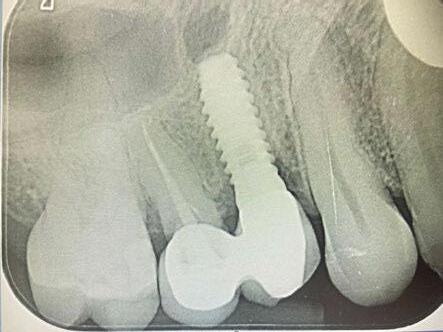

-Estudio radiográfico inicial (ortopantomografía y radiografías periapicales) (Figura 2).

Figura 2. Ortopantomografía inicial.

25, 26, 28, 37, 38, 47 y 48. Presentaba corona desajustada en 13 con extensión en 12, implantes en 35-36, 45-46, con coronas ferulizadas en 35-36, 45-46, y dientes anteriores superiores con enfermedad periodontal Grado IV.